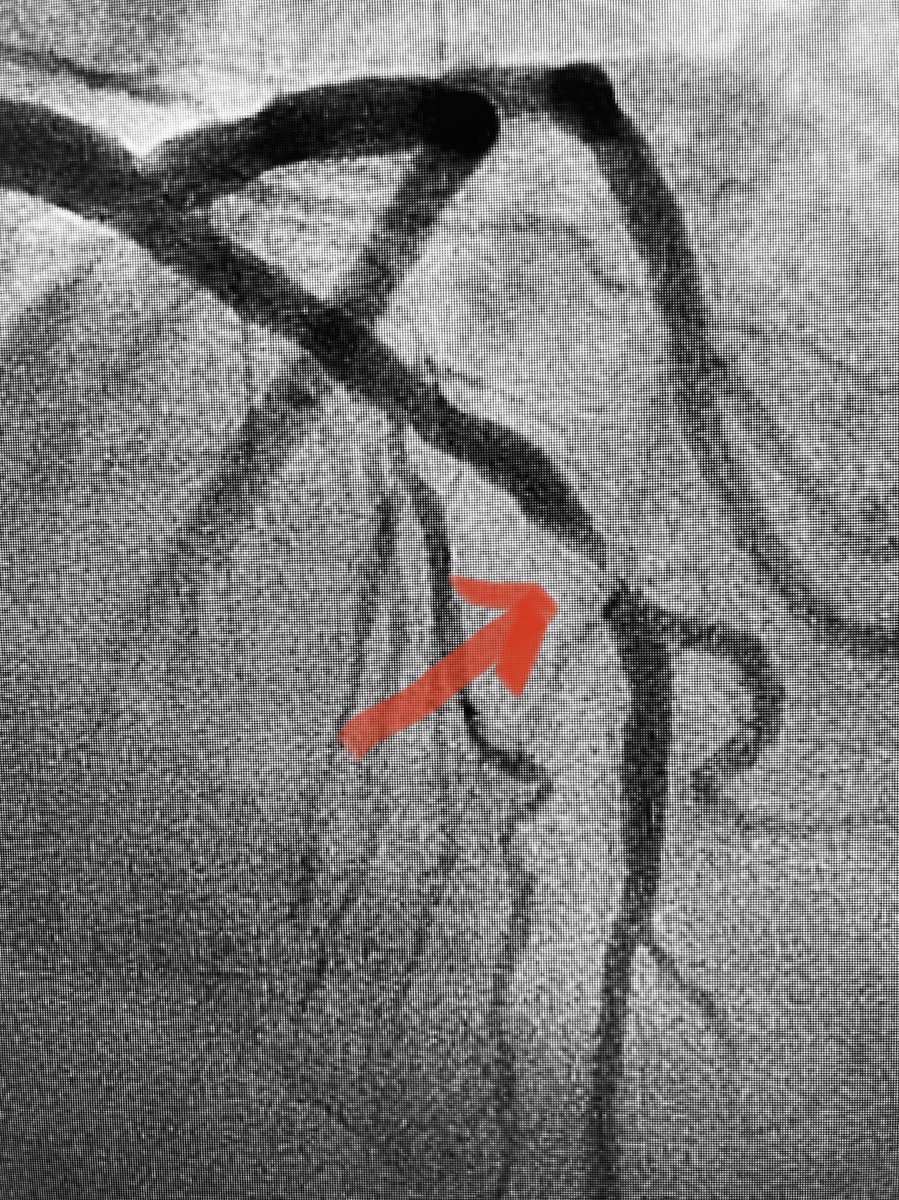

What #SCAD looks like on #OCT 👀 31 yo smoker w/ one day of intermittent CP worsened by exertion. EKG & echo normal but troponin positive. OCT done for lesion ambiguity: Thanks to @brandonjonesmd for sharing this case! #cardiotwitter #RadialFirst